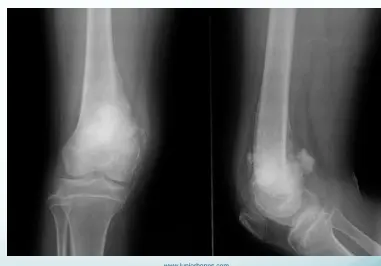

bone alignment

- subluxation of patella

- Anterior dislocation of shoulder joint

Patient â 40âyearâold female

Mechanism â Jumped from the 2nd floor

Presentation â Pain and swelling around the right knee

Site â Lateral tibial plateau

Type â Simple

Fracture line â Vertical split

Intraâarticular â Yes

Displacements â Small gap in the articular surface

Special issues â Requires surgery for absolute stability

A 32âyearâold patient fell from a palm tree and now presents with pain and swelling around the left knee.

- Site: Lateral tibial plateau

- Fracture type: Comminuted

- Fracture line: Vertical split

- Displacement: Depressed

- Special issues: CT scan required for detailed assessment

- Management needed: Surgical intervention